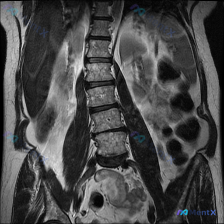

整理了一份腰椎MRI的读片讨论资料,先看冠状位T2加权像的客观表现:

- 脊柱排列:腰椎向左侧凸(Levoscoliosis),椎体有旋转,中轴线不平直

- 椎间盘:多节段下腰椎T2信号明显减低(“黑盘”征),提示脱水退变;凹侧(左侧)椎间隙更窄,有挤压

- 椎体/软组织:椎体边缘有骨赘;骨髓信号基本均匀,未见明确破坏;腰大肌对称尚可

- 潜在风险区:侧弯凹侧椎间孔/侧隐窝空间明显受限